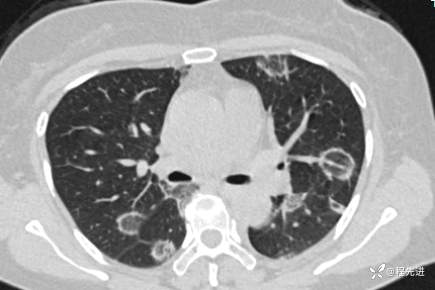

【心胸】特别精彩病例|胸闷1月余,好漂亮的反晕征呀

患者性别:女

患者年龄:57岁

简要病史:胸闷1月余

抗中性粒细胞胞质抗体相关性血管炎 (15)